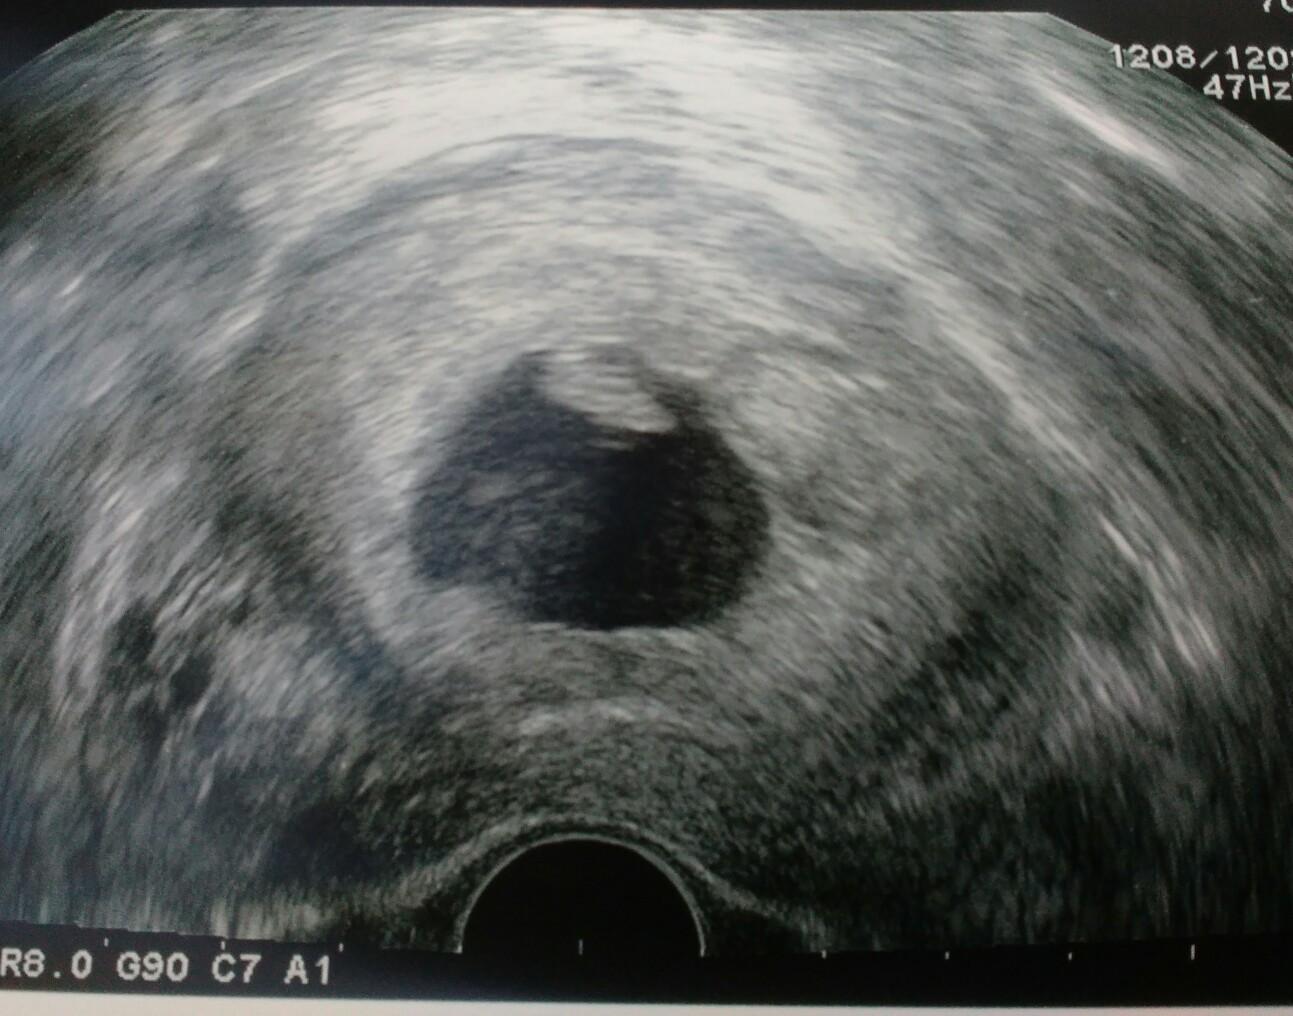

@snezenka123 omlouvam se, ze se vam do toho pletu holky. ja si taky prosla SP, mela jsem jen plodove vejce bez plodu. uz to bude asi dele nez 2 roky. tenkrat jsem chtela cekat, jestli to odejde samo a nesla na revizi. nastesti se to povedlo. pak jsem taky pila kontryhel a od dr. dostala konskou davku kyseliny listove. a druhy cyklus jsem otehotnela a vse bylo ok. drzim palce, vse bude zas dobre 🙂